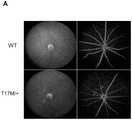

图5为T17M基因敲入小鼠眼底和血管造影图。Figure 5 is the fundus and angiogram of T17M gene knock-in mice.

由本发明的参照图5所示,通过眼底视网膜检测和血管造影(如图5,箭头指示)可以观察到T17M基因敲入小鼠视网膜眼底出现明显视网膜色素变性,视网膜动脉逐渐变细,并且出现串珠样改变。As shown in FIG. 5 in reference to the present invention, it can be observed that T17M gene knock-in mice have obvious retinitis pigmentosa in the retinal fundus of T17M gene knock-in mice by fundus retinal detection and angiography (indicated by arrows in FIG. 5 , retinal arteries are gradually thinned, and beading appears. kind of change.